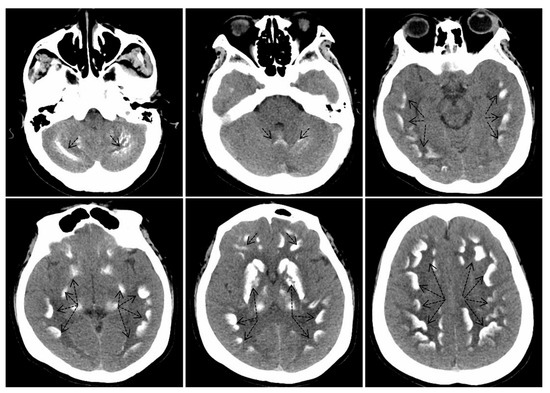

2.2. Biochemical and Radiographic Analysis